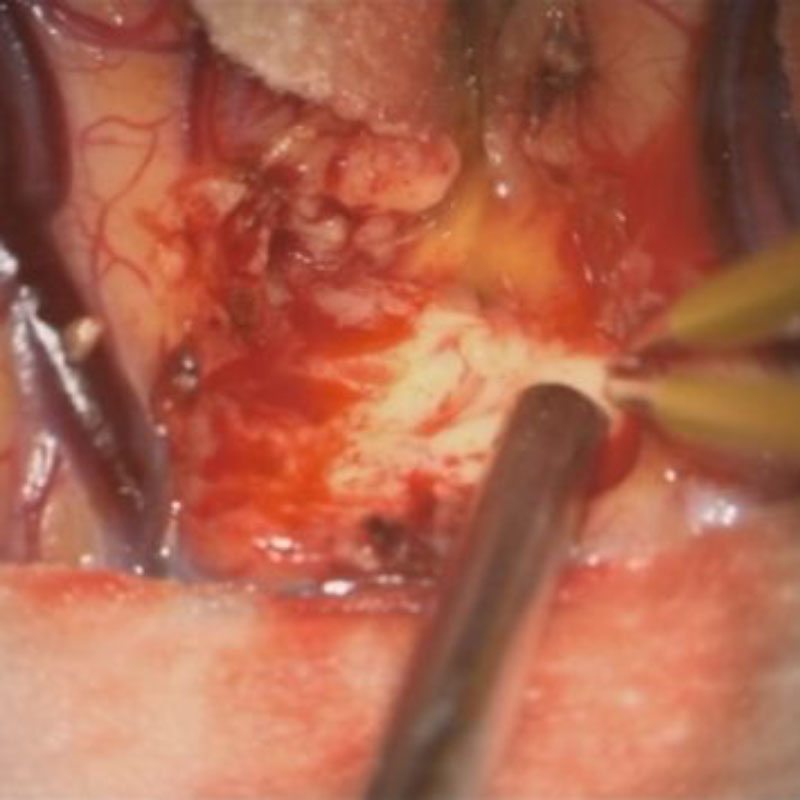

No.’25_26 摘出 前

No.’25_26  摘出 中